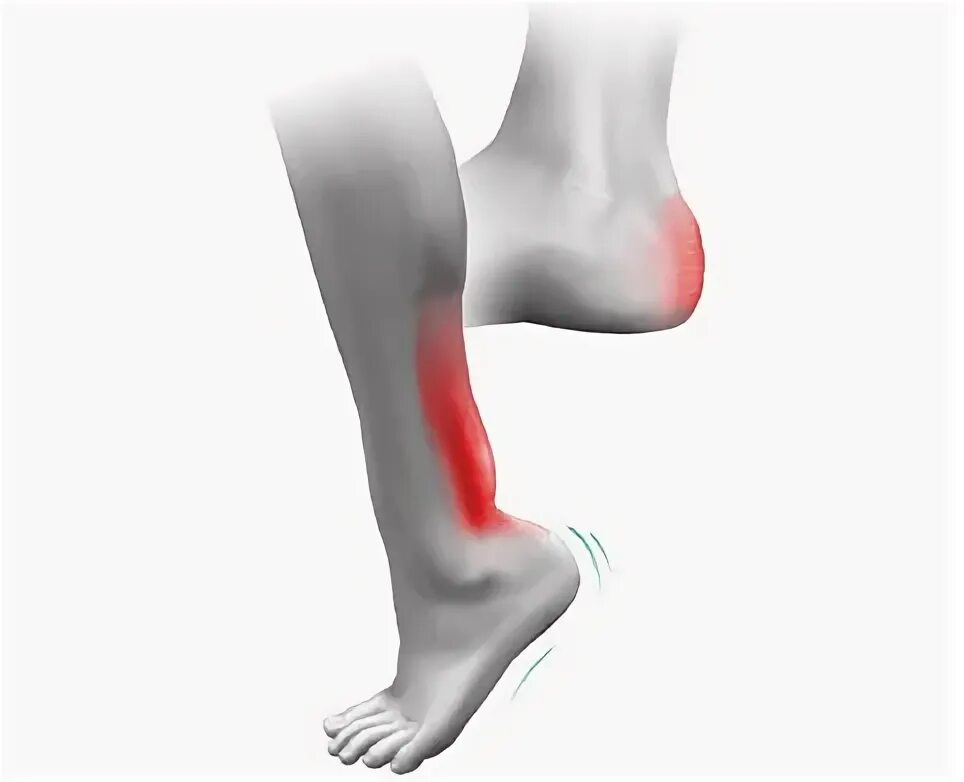

Ахиллобурсит мкб 10 у взрослых